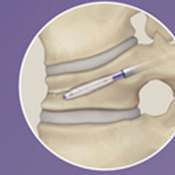

対象となる疾患は、脊椎圧迫骨折や転移性脊椎腫瘍による病的骨折などです。原則、手術翌日より軟性もしくは硬性のコルセットを装着し、起立・歩行を開始します。単独で行うこともありますが、固定術と一緒に行うこともあります。単独で行う場合には、全身麻酔下に約5mmの皮切2ヶ所から細い筒を骨折椎体に挿入し、人工骨やセメントを注入して、骨折を人工的に接合します。

BKP

風船をしぼめた状態で設置して、

ゆっくり風船を膨らませます。

復元します。

スペースにセメントを注入します。